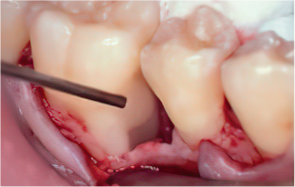

STEP 02

Scaling and Root Planing (SRP)

-

STEP 03

Removal of calculus and plaque